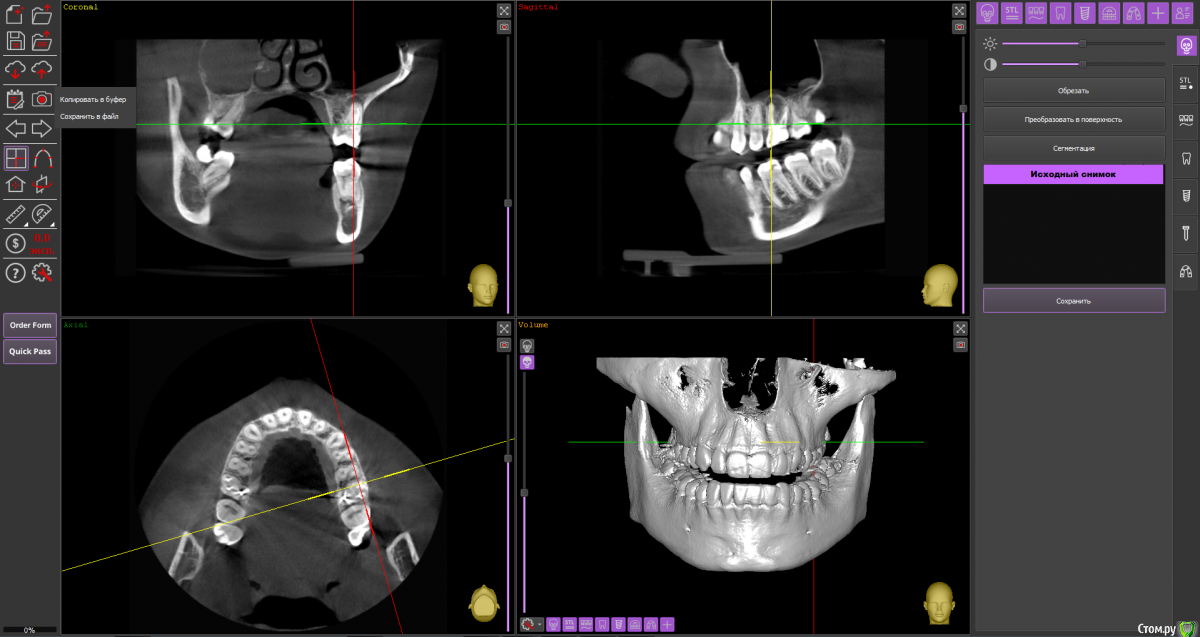

Ольга Вовк Опубликовано 10 февраля, 2021 Поделиться Опубликовано 10 февраля, 2021 Добрый день! Очень прошу помочь по таким вопросам:1. Верхняя шестерка справа - там киста перешедшая в гайморову пазуху (узнала это 4 месяца назад). Зуб ныл 2 года назад, тогда врач просто прописала Аугментин. Все прошло, но опять начал поднывать неделю назад (сейчас опять прошло). Была на консультации, сказали вырывать и прочищать пазуху нужно сейчас, и по приезду уже дальше разбираться. Как лучше быть, если я через неделю уезжаю на 4.5 месяца в страну, где никак не смогу продолжить лечение, а значит ставлю на паузу все на этот период.1. Удалить зуб сейчас, чтоб он зажил и через 4.5 месяца приехав сделать синус лифтинг и ставить имплант, или же ждать это время не удаляя зуб? 2. Не разрушится ли если сейчас не вырвать полностью костная ткань? 3. Можно ли не ставить имлпант, а сдвинуть 7 и 8 зуб к 5ому? Также вопрос по верхней шестерке слева - можно ли ее перелечить под микроскопом, или нужно делать резекцию? Разные врачи сделали разные выводы по нему Ссылка на архив файлов панорамного КТ - http://fayloobmennik.cloud/7414975 Спасибо вам, очень надеюсь на совет Ссылка на комментарий

Ольга Вовк Опубликовано 10 февраля, 2021 Автор Поделиться Опубликовано 10 февраля, 2021 16_1.png 16_2.png 16_3.png 26_1.png 26_2.png 26_3.png 26_4.png Зуб 16, мне кажется, лучше удалить до отъезда. Насчёт ортодонтического перемещения 8-го и 7-го на место 6-го, необходимо с ортодонтом очно пообщаться, но на мой взгляд, хирургическое лечение будет более предсказуемым.Зуб 26 может оказаться непростым для эндодонтиста, но если доктор берётся и Вы ему доверяете, то начать стоит с повторного эндодонтического лечения с увеличением.Спасибо вам огромное! Я так понимаю, что если не удалить сейчас, то тогда к приезду (3 июля) уже совсем костной ткани не останется? Просто если сейчас удалить и будут осложнения, или соустье в гайморову, то я уеду и там не знаю что буду делать в такой ситуации(( Ссылка на комментарий